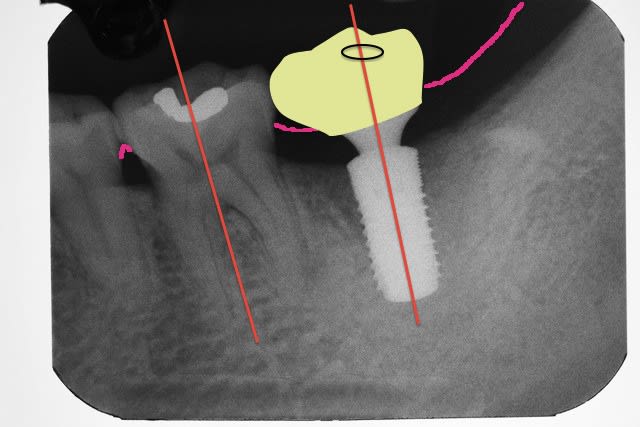

fric fric fric !

l'étude de cas et les guides chir au départ rendent l'implantologie peu rentable apparemment